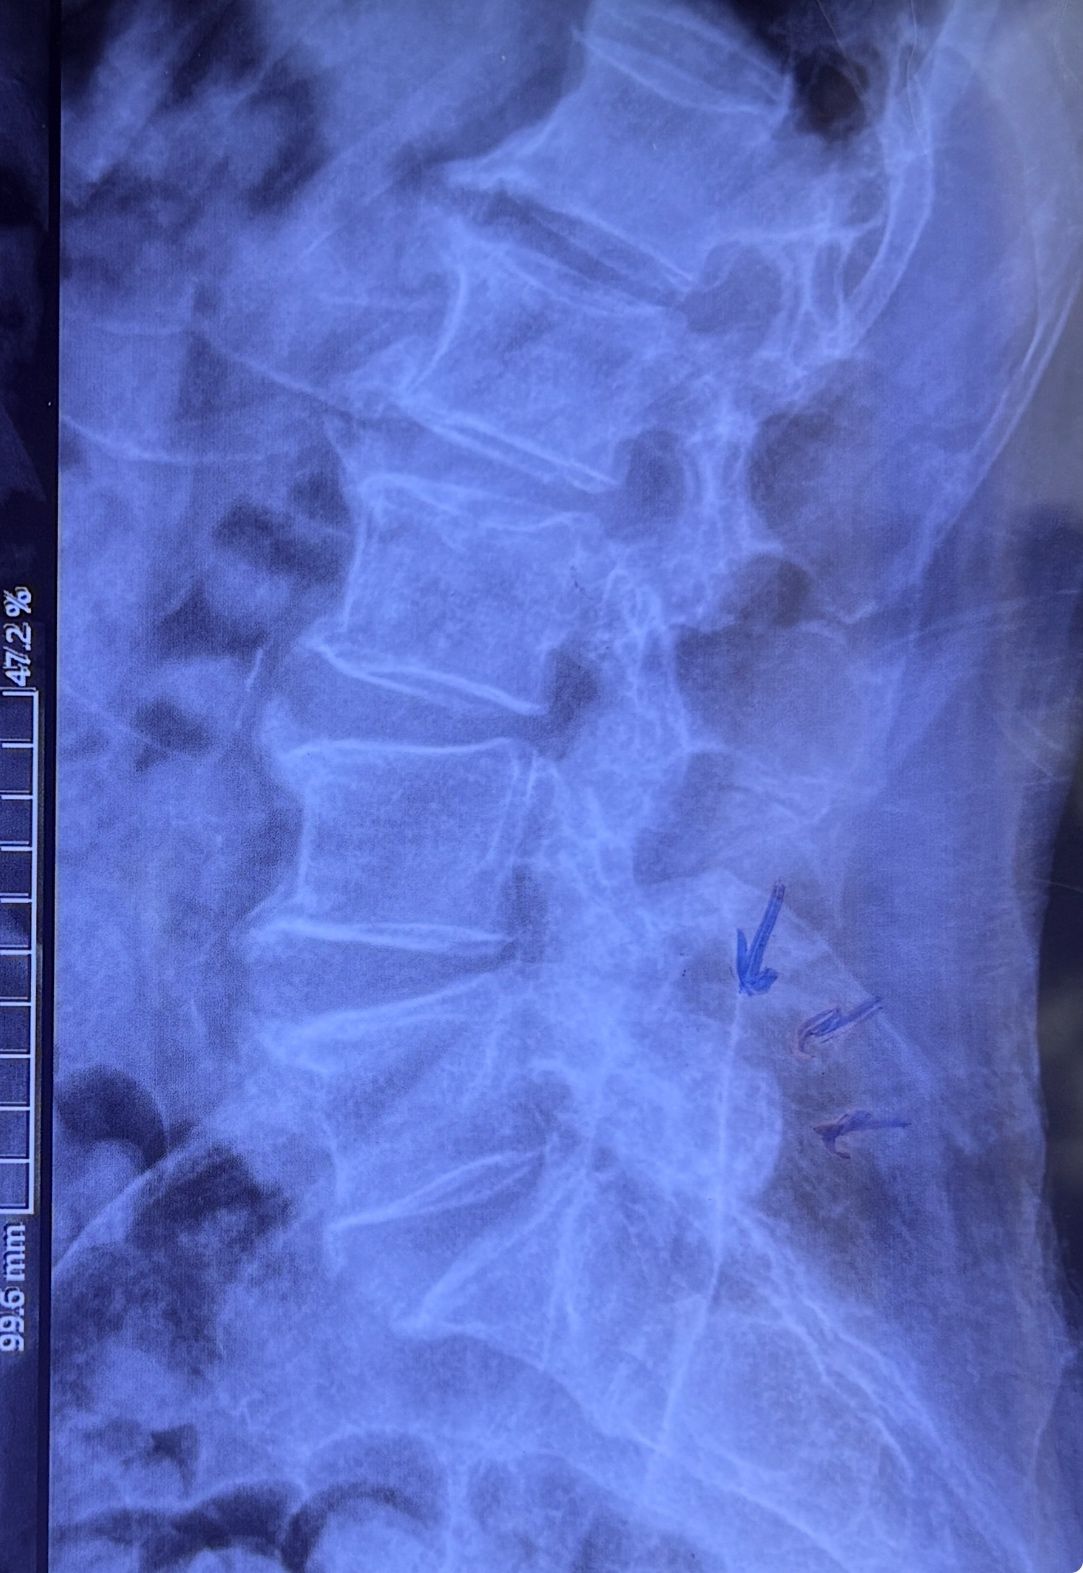

This time presented to my cl with LBP mainly during sleep at night. Just brought me her mri. According to her mri I ordered dynamic L/S X. R.

I didn’t accept her to give treatment. I referred her to her surgeon. What are your findings in her mri and X. Rays?

Is ant listhesis of L4 unstable or stable?

From several compression fractures we see which of is acute/ subacute and which ones are chronic fx?